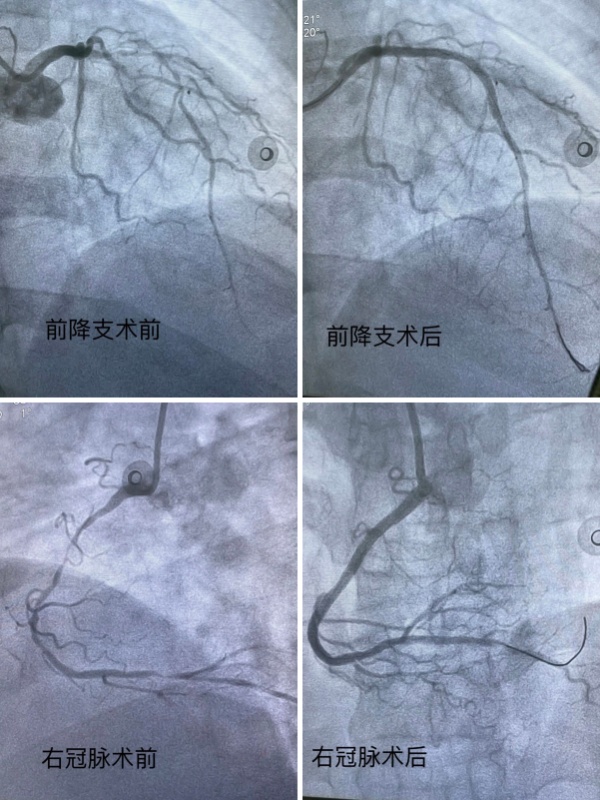

为确保患者安全,詹小娜前往急诊等候急救车。在接到患者后,她第一时间为患者进行冠脉造影检查,显示患者前降支、回旋支及右冠状动脉均存在超过90%的严重狭窄,且病变弥漫,斑块不稳定,为高危“三支病变”。詹小娜立即向患者及家属解释,这种情况下心肌处于严重缺血状态,随时可能因恶性心律失常导致猝死。经过患者及家属同意后,詹小娜随即为患者施行紧急介入治疗,开通堵塞血管,术后观察3天,患者在走廊活动已完全无症状,目前已平安出院。